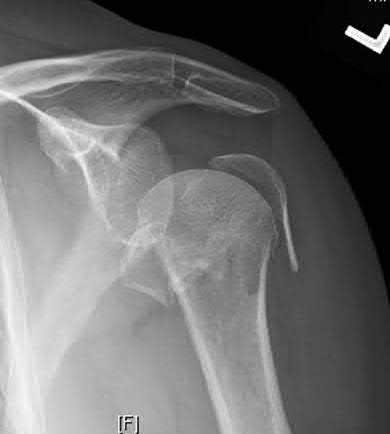

A 70-year-old woman falls down a flight of stairs and sustains the injury shown in Figures A and B to her dominant upper extremity. She lives alone and has no other medical history. Which of the following surgical options is best to minimize complications for this fracture pattern?

This patient has a complex proximal humerus fracture with metaphyseal comminution and poor bone stock. Cemented reverse total shoulder arthroplasty (rTSA) using a long stem prosthesis and tuberosity repair is indicated.

Proximal humerus fragility fractures are hard to treat because of comminution and poor bone stock. AVN is common with glenohumeral fracture-dislocation. Hemiarthroplasty (and standard total shoulder arthroplasty, TSA) is unreliable because of dependence on tuberosity healing. rTSA is recommended for fractures in patients >70 years with severely comminuted fractures, high likelihood of head AVN, and poor tuberosity bone quality (osteoporosis or comminution).

Bufquin et al. retrospectively reviewed the use of rTSA for treatment of 43 patients with 3- and 4-part proximal humerus fractures. They found satisfactory elevation (97°), ER in abduction (30°), constant scores (44) and modified Constant scores (66%). Complications included calcification (90%), tuberosity displacement (53%) and scapular notching (25%). They concluded that rTSA was a good procedure because it provides pain relief and easier functional recovery in spite of failed tuberosity healing.

Anakwenze et al. systematically reviewed acute proximal humerus fractures. Frequency weighted range of motion was flexion 122°, abduction 97°, ER at neutral 18°. Tuberosity repair yielded higher ER compared to no repair.

Scapular notching was the most common complication (32%). They concluded that rTSA patients tended to be elderly women with 4-part fractures, had good pain control but residual dysfunction.

Jobin et al. reviewed rTSA for management of proximal humerus 3- and 4-part fractures. They note >50% of cases have tuberosity resorption. They recommend repairing the greater tuberosity to restore infraspinatus/teres minor function which improves external rotation strength. Greater tuberosity malunion is not a result of secondary displacement, but rather, from intraoperative malreduction. Lesser tuberosity repair should be performed if there is significant bone loss or intraoperative anterior instability.

Figures A and B are AP radiograph and 3D reformatted CT scan showing comminuted proximal humerus fracture dislocation. Illustration A shows rTSA performed with distal cementation of a long stem prosthesis and cerclage fixation of the proximal shaft and the tuberosity fragments.

Incorrect Answers:

Answer 1: ORIF has potential complications of screw cut out, AVN, fracture collapse, tuberosity resorption and loss of fixation. The risk of AVN (and resultant screw cut out) is high because of comminuted fracture-dislocation. Answer 2: Cementing is indicated because metaphyseal fracture bone loss compromises stem fixation.

Answer 3: Greater tuberosity repair improves external rotation strength. Lesser tuberosity repair adds to anterior stability.

Answer 5: Proximal humeral replacement is only necessary for tumor or unreconstructable fractures. They have poorer outcomes because of loss of rotator cuff function.